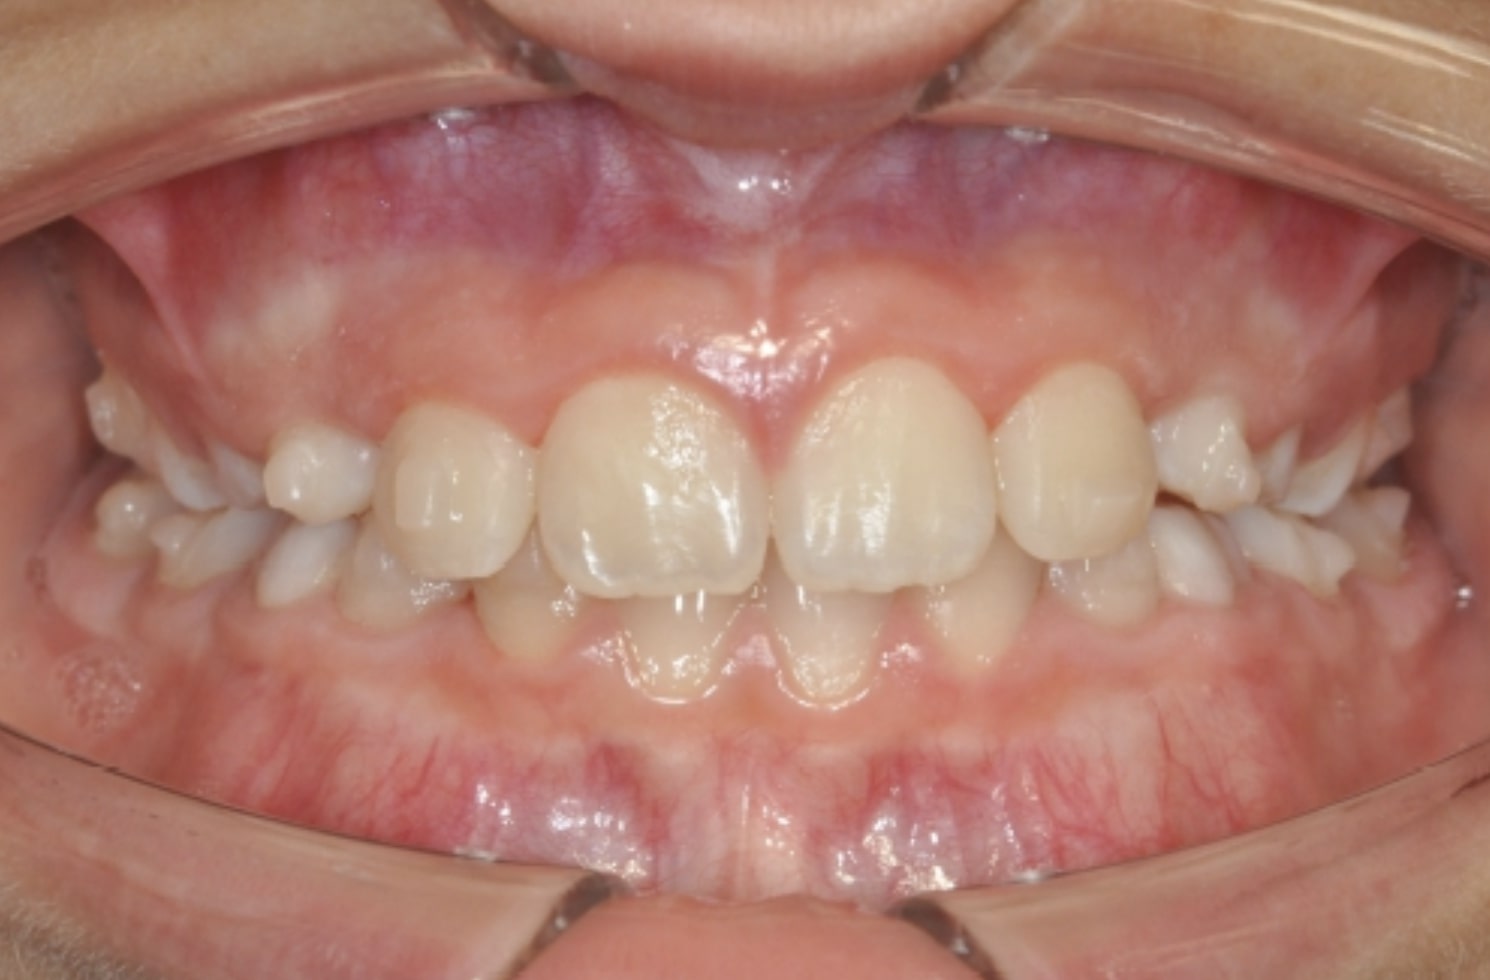

Correction of mandibular retrusion in growing patients with A6 mandibular advancement

By Dr. Giacomo Scuzzo

This case showcases an innovative approach to correcting lower jaw retrusion in growing patients using the Angel Aligner A6. The system combines orthopedic and orthodontic treatment into a single protocol, allowing simultaneous advancement of the lower jaw and alignment of teeth. With digital planning and aesthetic aligners, the treatment is both effective and comfortable for the patient. This case was managed by Dr. Giacomo Scuzzo